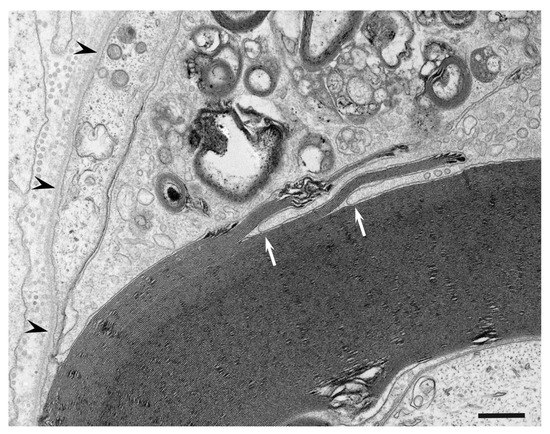

Macrophages and Autoantibodies in Demyelinating Diseases

Myelin phagocytosis by macrophages has been an essential feature of demyelinating diseases in the central and peripheral nervous systems, including Guillain–Barré syndrome (GBS), chronic inflammatory demyelinating polyneuropathy (CIDP), and multiple sclerosis (MS). The discovery of autoantibodies, including anti-ganglioside GM1 antibodies in the axonal [...] Read more.

Myelin phagocytosis by macrophages has been an essential feature of demyelinating diseases in the central and peripheral nervous systems, including Guillain–Barré syndrome (GBS), chronic inflammatory demyelinating polyneuropathy (CIDP), and multiple sclerosis (MS). The discovery of autoantibodies, including anti-ganglioside GM1 antibodies in the axonal form of GBS, anti-neurofascin 155 and anti-contactin 1 antibodies in typical and distal forms of CIDP, and anti-aquaporin 4 antibodies in neuromyelitis optica, contributed to the understanding of the disease process in a subpopulation of patients conventionally diagnosed with demyelinating diseases. However, patients with these antibodies are now considered to have independent disease entities, including acute motor axonal neuropathy, nodopathy or paranodopathy, and neuromyelitis optica spectrum disorder, because primary lesions in these diseases are distinct from those in conventional demyelinating diseases. Therefore, the mechanisms underlying demyelination caused by macrophages remain unclear. Electron microscopy studies revealed that macrophages destroy myelin as if they are the principal players in the demyelination process. Recent studies suggest that macrophages seem to select specific sites of myelinated fibers, including the nodes of Ranvier, paranodes, and internodes, for the initiation of demyelination in individual cases, indicating that specific components localized to these sites play an important role in the behavior of macrophages that initiate myelin phagocytosis. Along with the search for autoantibodies, the ultrastructural characterization of myelin phagocytosis by macrophages is a crucial step in understanding the pathophysiology of demyelinating diseases and for the future development of targeted therapies. Full article